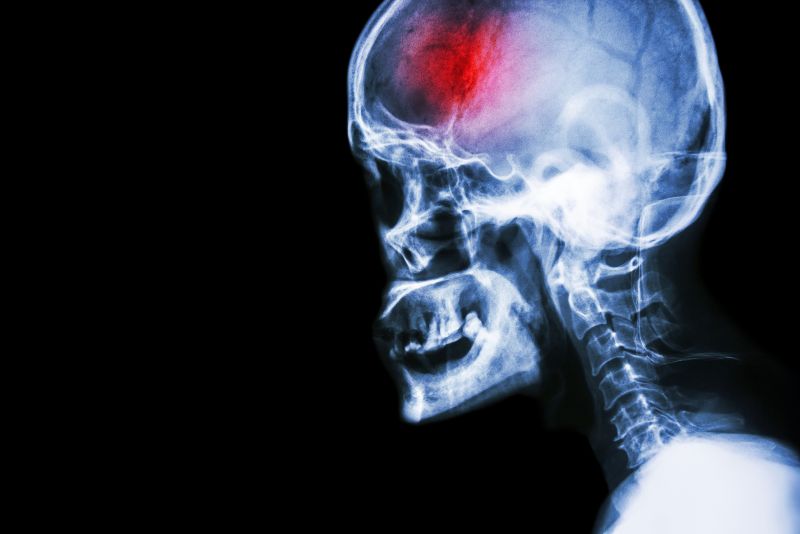

Head X-ray

Head X-rayA stroke is a serious medical emergency that requires immediate action in order to achieve the best eventual outcomes. Early medical intervention, as well as early, consistent and ongoing rehabilitation will positively affect your long term capabilities.  Physical therapy services at FYZICAL Lexington can assist you to recover from your stroke and regain your maximum potential.